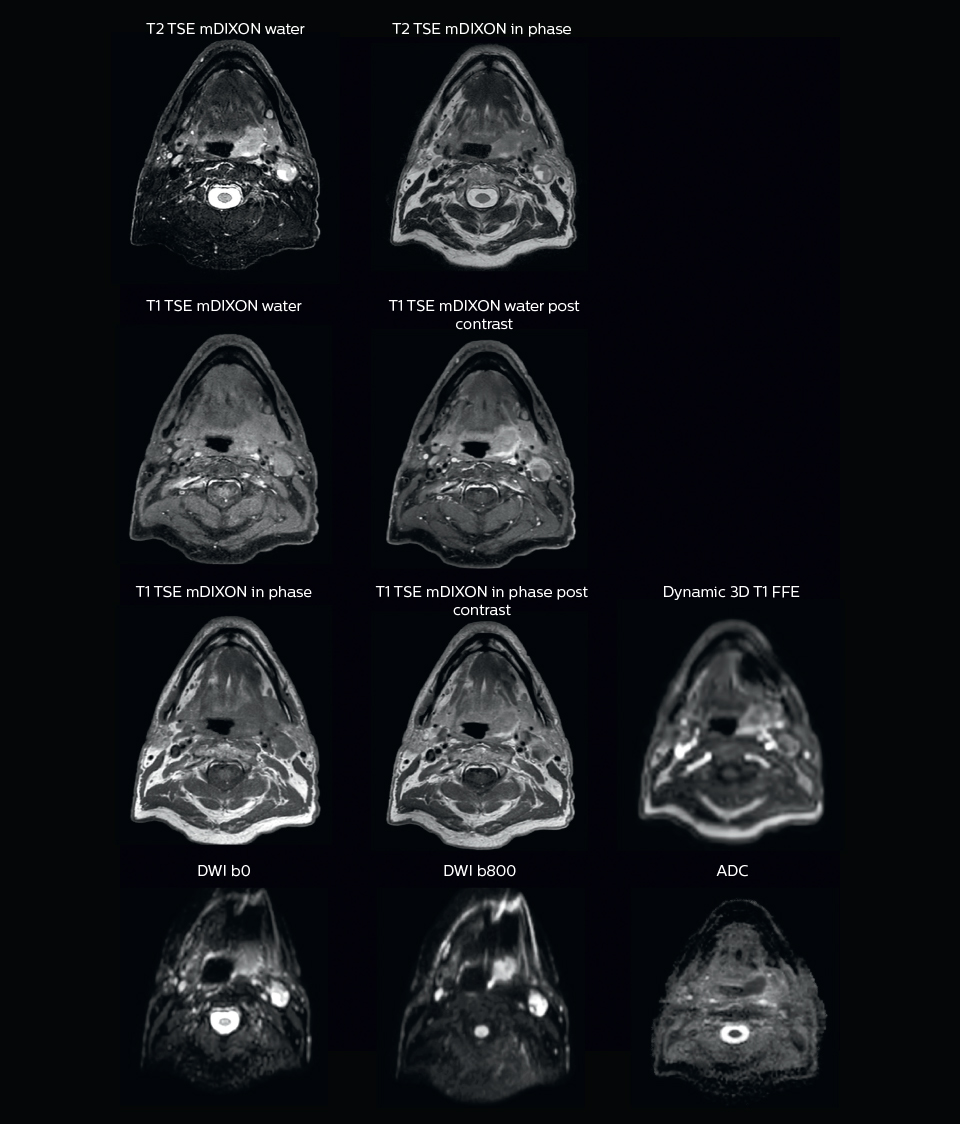

“In patients with a primary tumor in the head and neck area, we do use MRI in daily clinical radiation therapy practice to visualize the tumor and critical structures. This may be used to help sparing of critical structures, such as the parotid glands, submandibular glands, esophagus, optic nerves, brain stem and spinal cord [7]. And postoperatively we scan patients that have tumor growth along the cranial nerves for target delineation,” says Dr. Philippens.

“We use pre- and post-contrast T1- and T2-weighted sequences with the fast and robust mDIXON method for fat suppression,” says Dr. Philippens. “Dynamic contrast-enhanced imaging is performed with high temporal resolution and low spatial resolution, to see the contrast agent uptake in the tumor. Diffusion weighted imaging is used qualitatively to see how the tumor extends into another structure, rather than for strict delineation.”

“In postoperative patients who have had tumor growth along the cranial nerves, we use T2-weighted gradient echo (FFE) on our 3.0T MR-RT scanner to show the nerves for target delineation and look to see if there is still tumor left.”